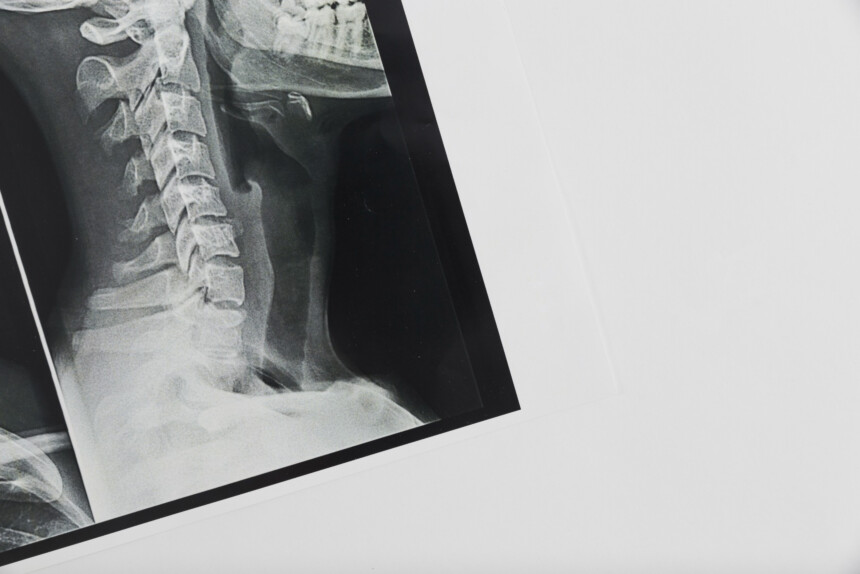

TOMOGRAFIA PESCOÇO (PARTES MOLES, LARINGE, TIREÓIDE E FARINGE)